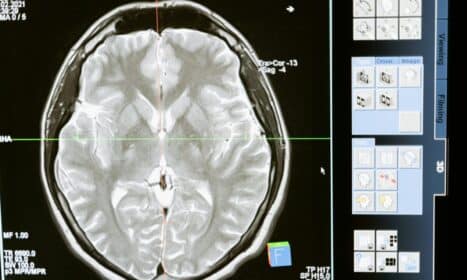

Sveikata Nauja viltis sergantiems Hantingtono liga: genų terapija gali sustabdyti smegenų žalą prieš simptomus Vytautas Strazdas • 2026-01-24